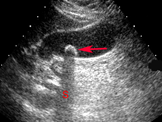

Ha szeretné fokozni agyának vérellátását érdemes kipróbálnod a Ginkgo Bilobát, amely köztudottan növeli az agy vérkeringését, ezáltal segíti a mentális teljesítményt. A dolgozatomban leírásra került, hogy az agyi működésben/vérkeringésben melyek okoznak zavart. Olvashat a mini sztrókról (TIA) és annak okiról. TIA esetén az érintett agyterület zavara miatt specifikus ideggyógyászati tünetek jelennek meg. A vérrög a szívből is kerülhet az agyi erekbe. Megtudhatja, hol és kinél jelentkezhet TIA vizsgálatára. Agyi károsodás súlyos májbetegség (pl. májzsugor, májelégtelenség) következtében jelentkezik. A fibroscan vizsgálatot (foto) végző szakorvos elérhetősége is leírásra került.

hol és kinél jelentkezhet TIA vizsgálatára. Agyi károsodás súlyos májbetegség (pl. májzsugor, májelégtelenség) következtében jelentkezik. A fibroscan vizsgálatot (foto) végző szakorvos elérhetősége is leírásra került.